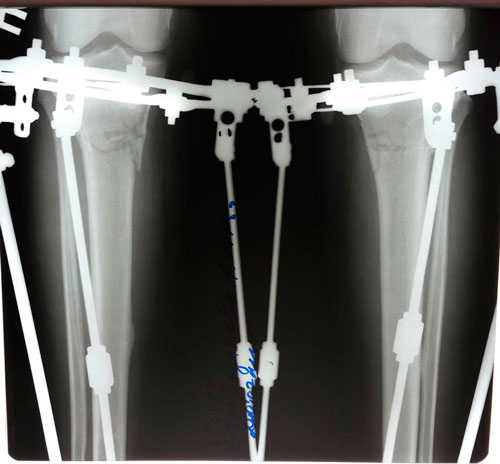

Исходник -34 года.Бишкек.

Дата операции - 26.02.2019г.

Дата снятия аппаратов - 05.06.2019г.

Срок сращения - 98 дней.